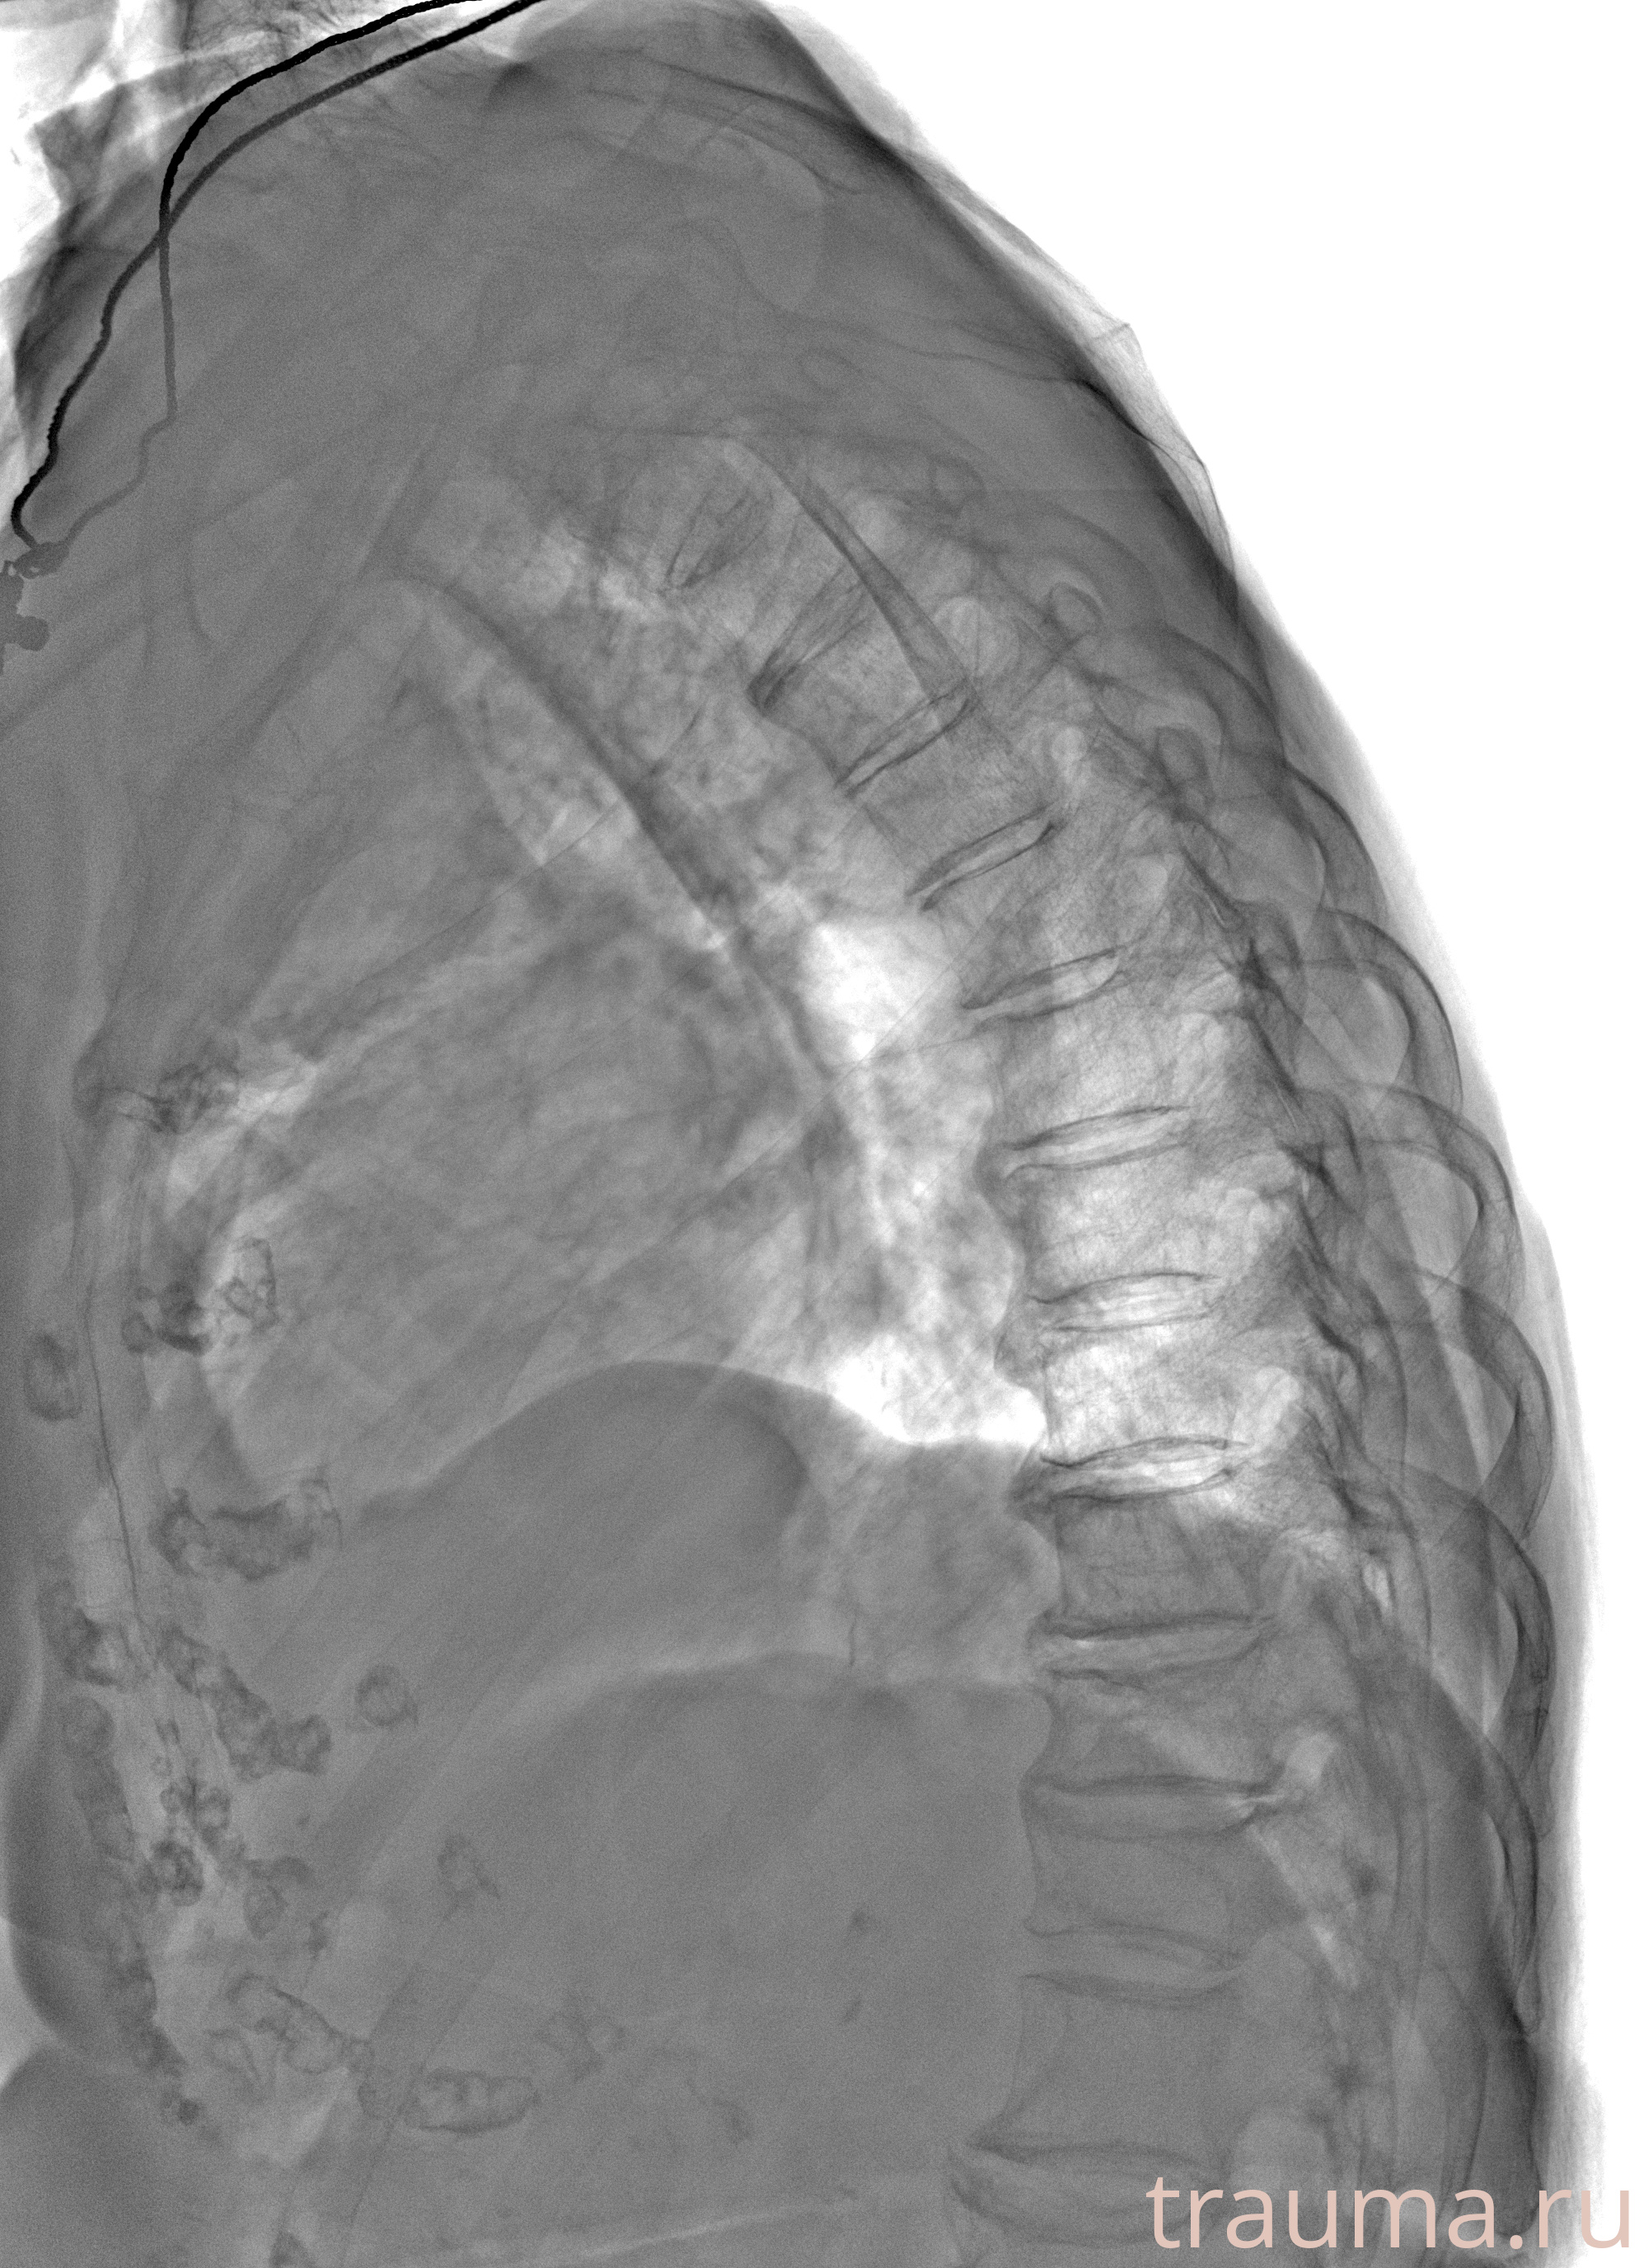

Рентген на дому: по вашему адресу приезжает врач-рентгенолог, травматолог-ортопед с мобильным рентгеновским аппаратом, проводит диагностику травмы или заболевания, делает необходимые рентгенограммы, дает рекомендации по дальнейшему лечению. Получить качественные снимки в домашних условиях возможно благодаря уникальной методике, разработанной МосРентген Центром для института  Склифосовского

при переломе шейки бедра и пневмонии от компании МосРентген Центр - партнера Института имени Склифосовского